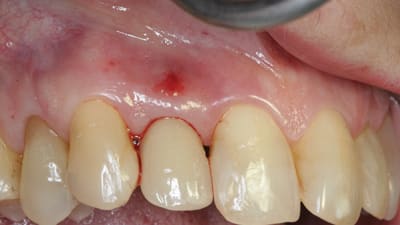

Clinical Technique Review Implantology Double-up Technique for Correction of Ridge Contour Deficiencies By Rodrigo Neiva, DDS, Vinay Bhide, DDS July 15, 2022 12 min read